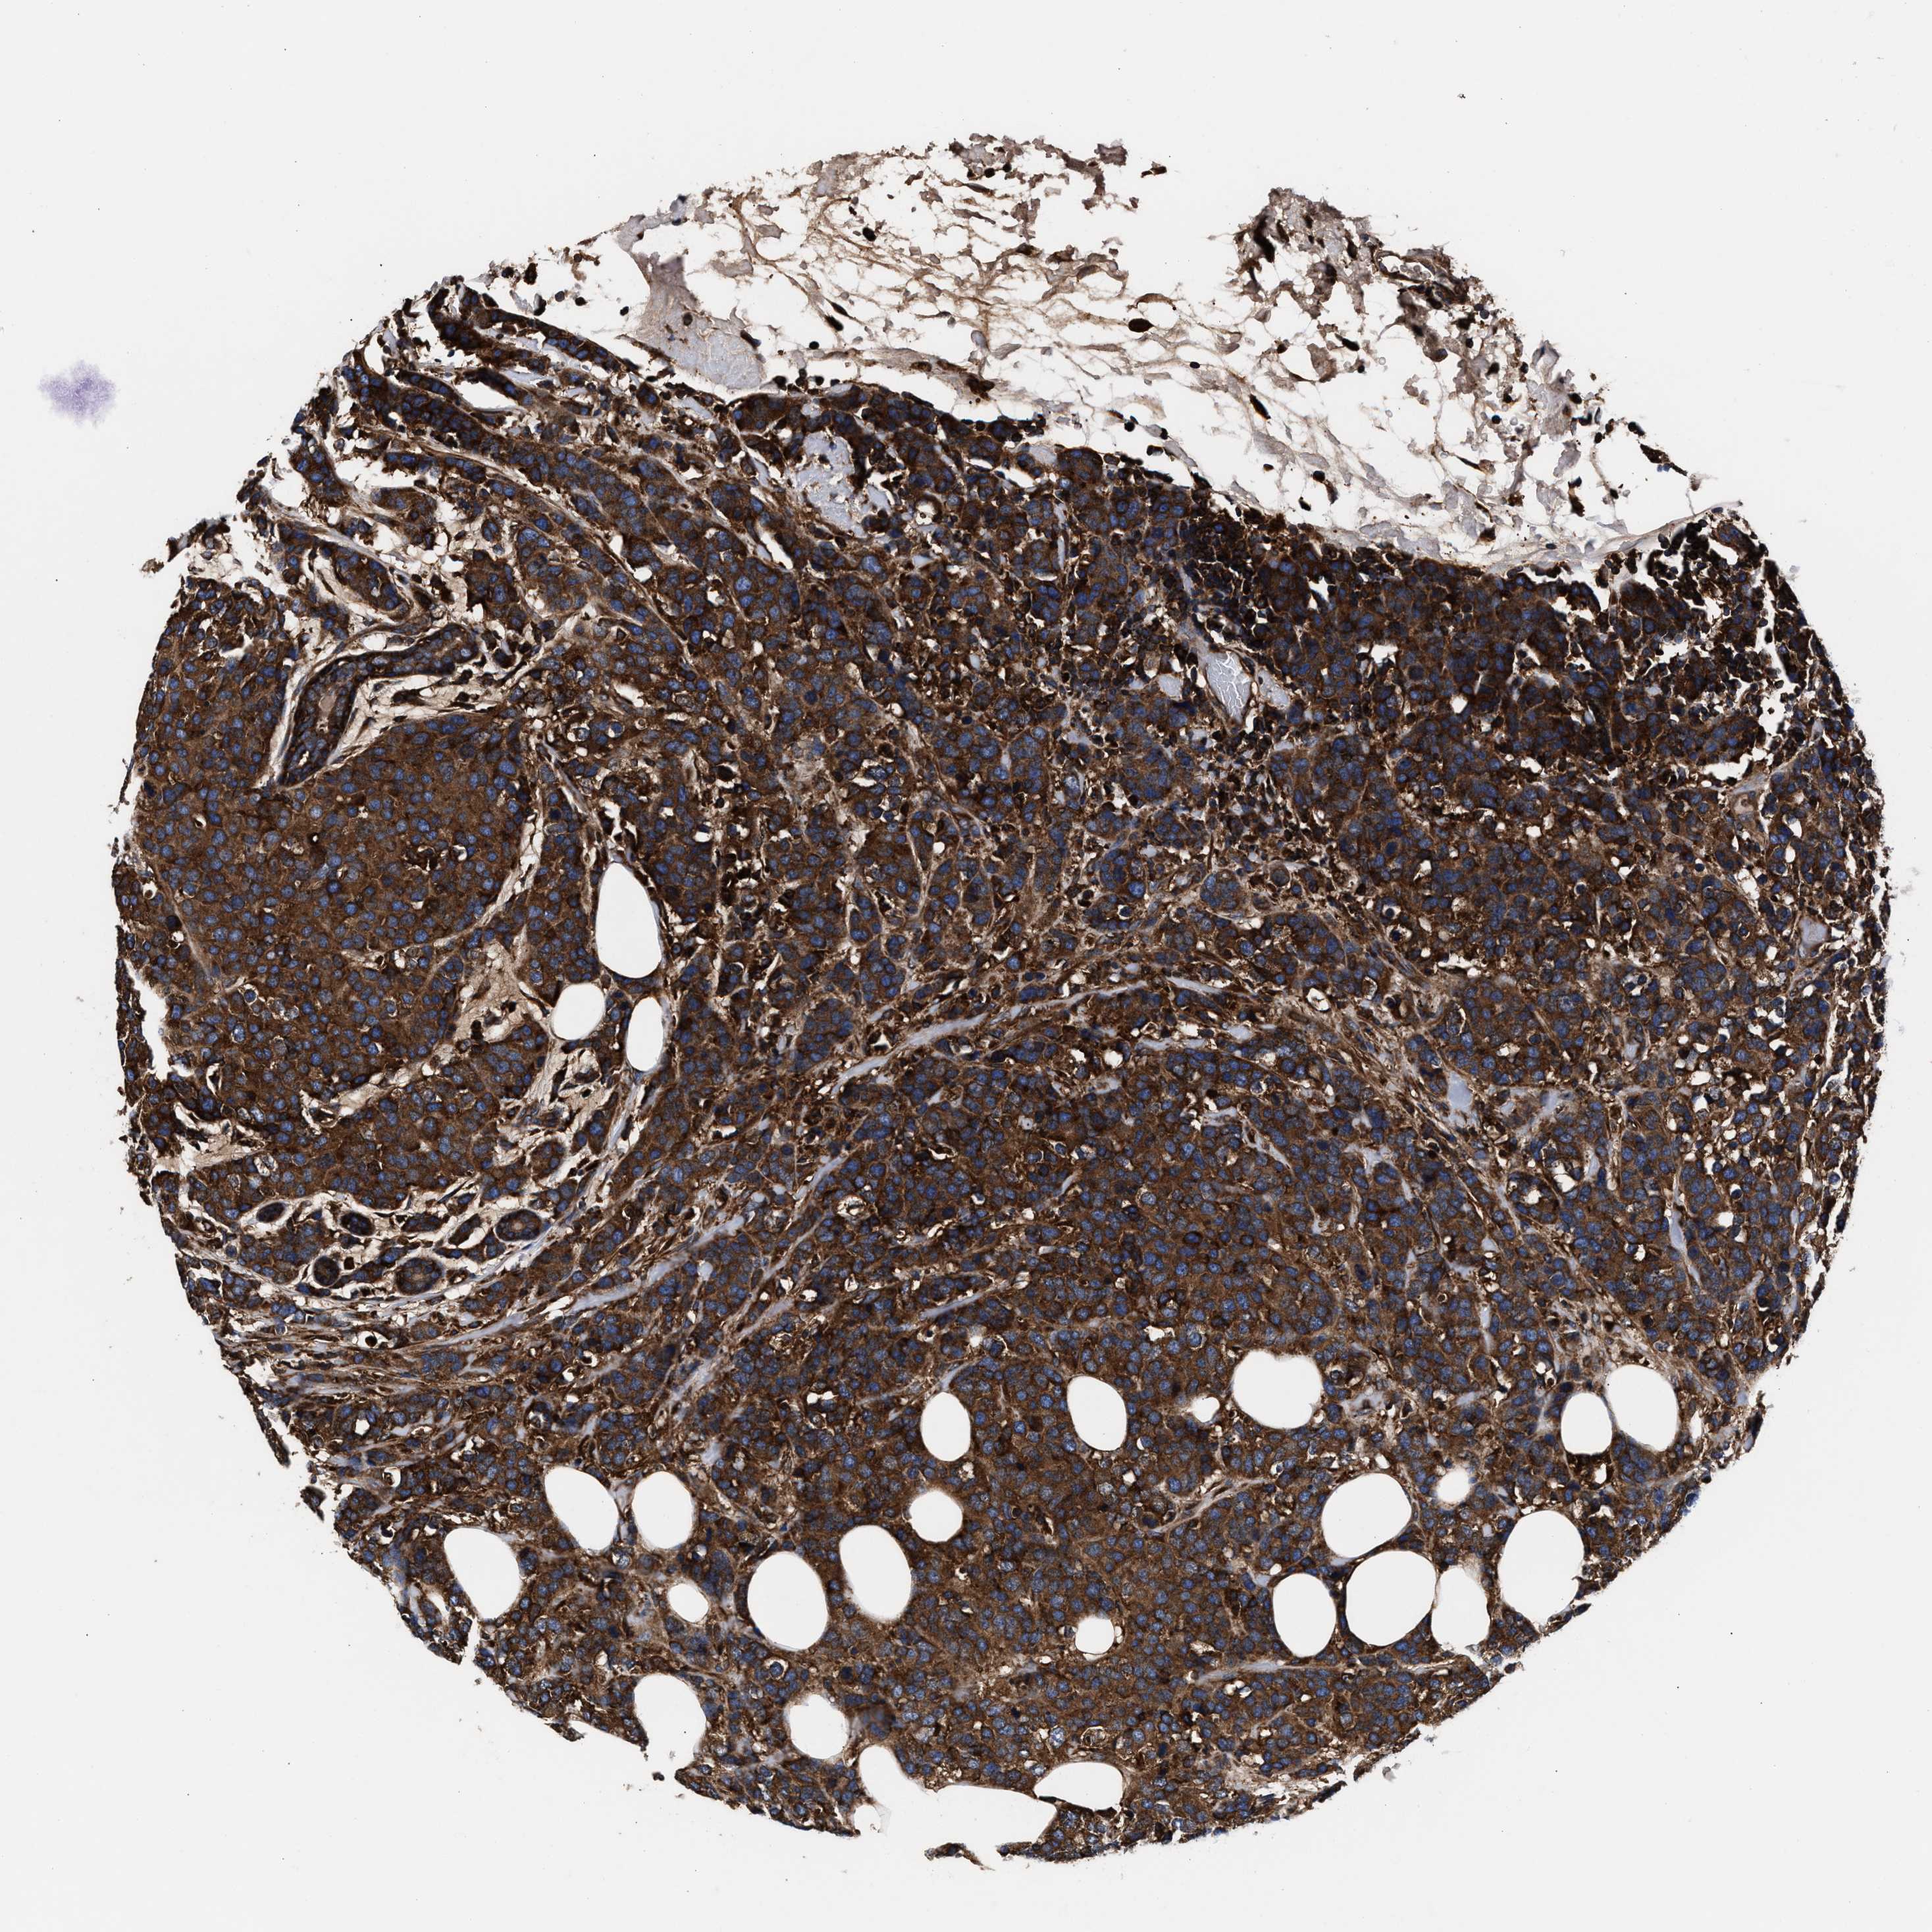

BRCA TCGA BRCA VALIDATION PROTEIN EXPRESSION

ANTIBODIES

AND

VALIDATION